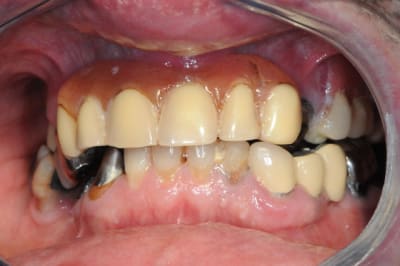

dentiste57

je ne voudrais pas "louper " ce cas, alors quelles idées de traitements auriez vous à me soumettre ?

pas de pb de santé

portefeuille pas extensible...